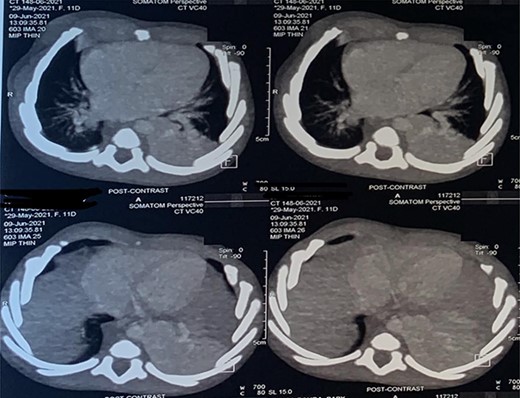

A 6-month-old male baby who was found to have fetal adenomatoid malformation from a prenatal ultrasound (US) done at 20 weeks’ gestation and polyhydramnios at 30 weeks’ gestation (Fig. 1) is reported. The mass measured 4.7 × 4.1 × 3.5 cm with no evidence of systemic feeding artery, associated anomalies or hydrops at 24 weeks. Cesarean delivery was done at 38 weeks’ gestation for severe polyhydramnios. He spent first 3 weeks at the neonatology unit with respiratory distress and again on sixth week of life for pneumonia. A chest computed tomography (CT) scan (Fig. 2) at 2 weeks showed a wedge-shaped homogenously enhancing mass measuring 4.8 × 2.8 × 1.8 cm in the left lower lobe with an aberrant arterial branch from the descending thoracic at T12. Cardiothoracic surgery reviewed and maintained patient for surgery. He had normal preoperative laboratory work-up and underwent aberrant artery ligation and resection of the sequestrated lung via standard left posterolateral thoracotomy.

CT scan images depicting intralobar pulmonary sequestration of the left lower lung lobe.